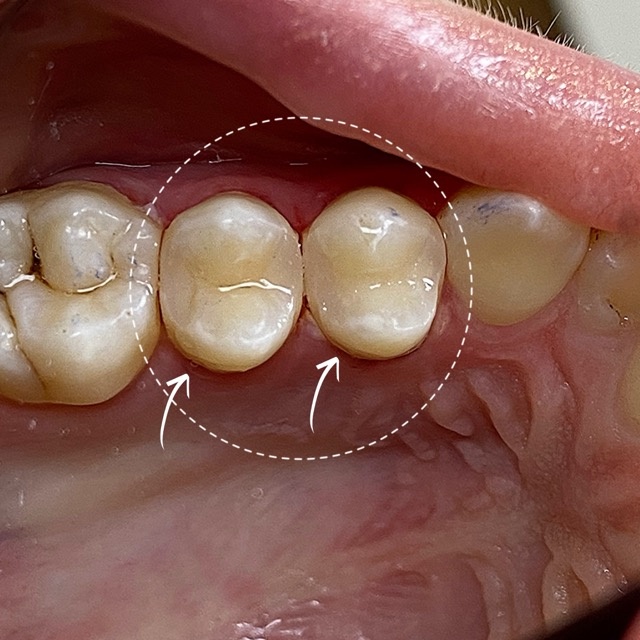

Художественная реставрация зубов 24,25

При изучении КТ снимка были выявлены кариозные поражения на контактных поверхностях 2.4 и 2.5 зубов. Жизнеспособность пульпы сохранена. Диагноз: кариес дентина. В процессе лечения выполнено вскрытие полостей, механическо-химическая обработка, восстановление контактных пунктов.

После, произведена художественная реставрация. Время лечения: полтора часа. Стоимость лечения двух зубов за одно посещение: 14.600 рублей.